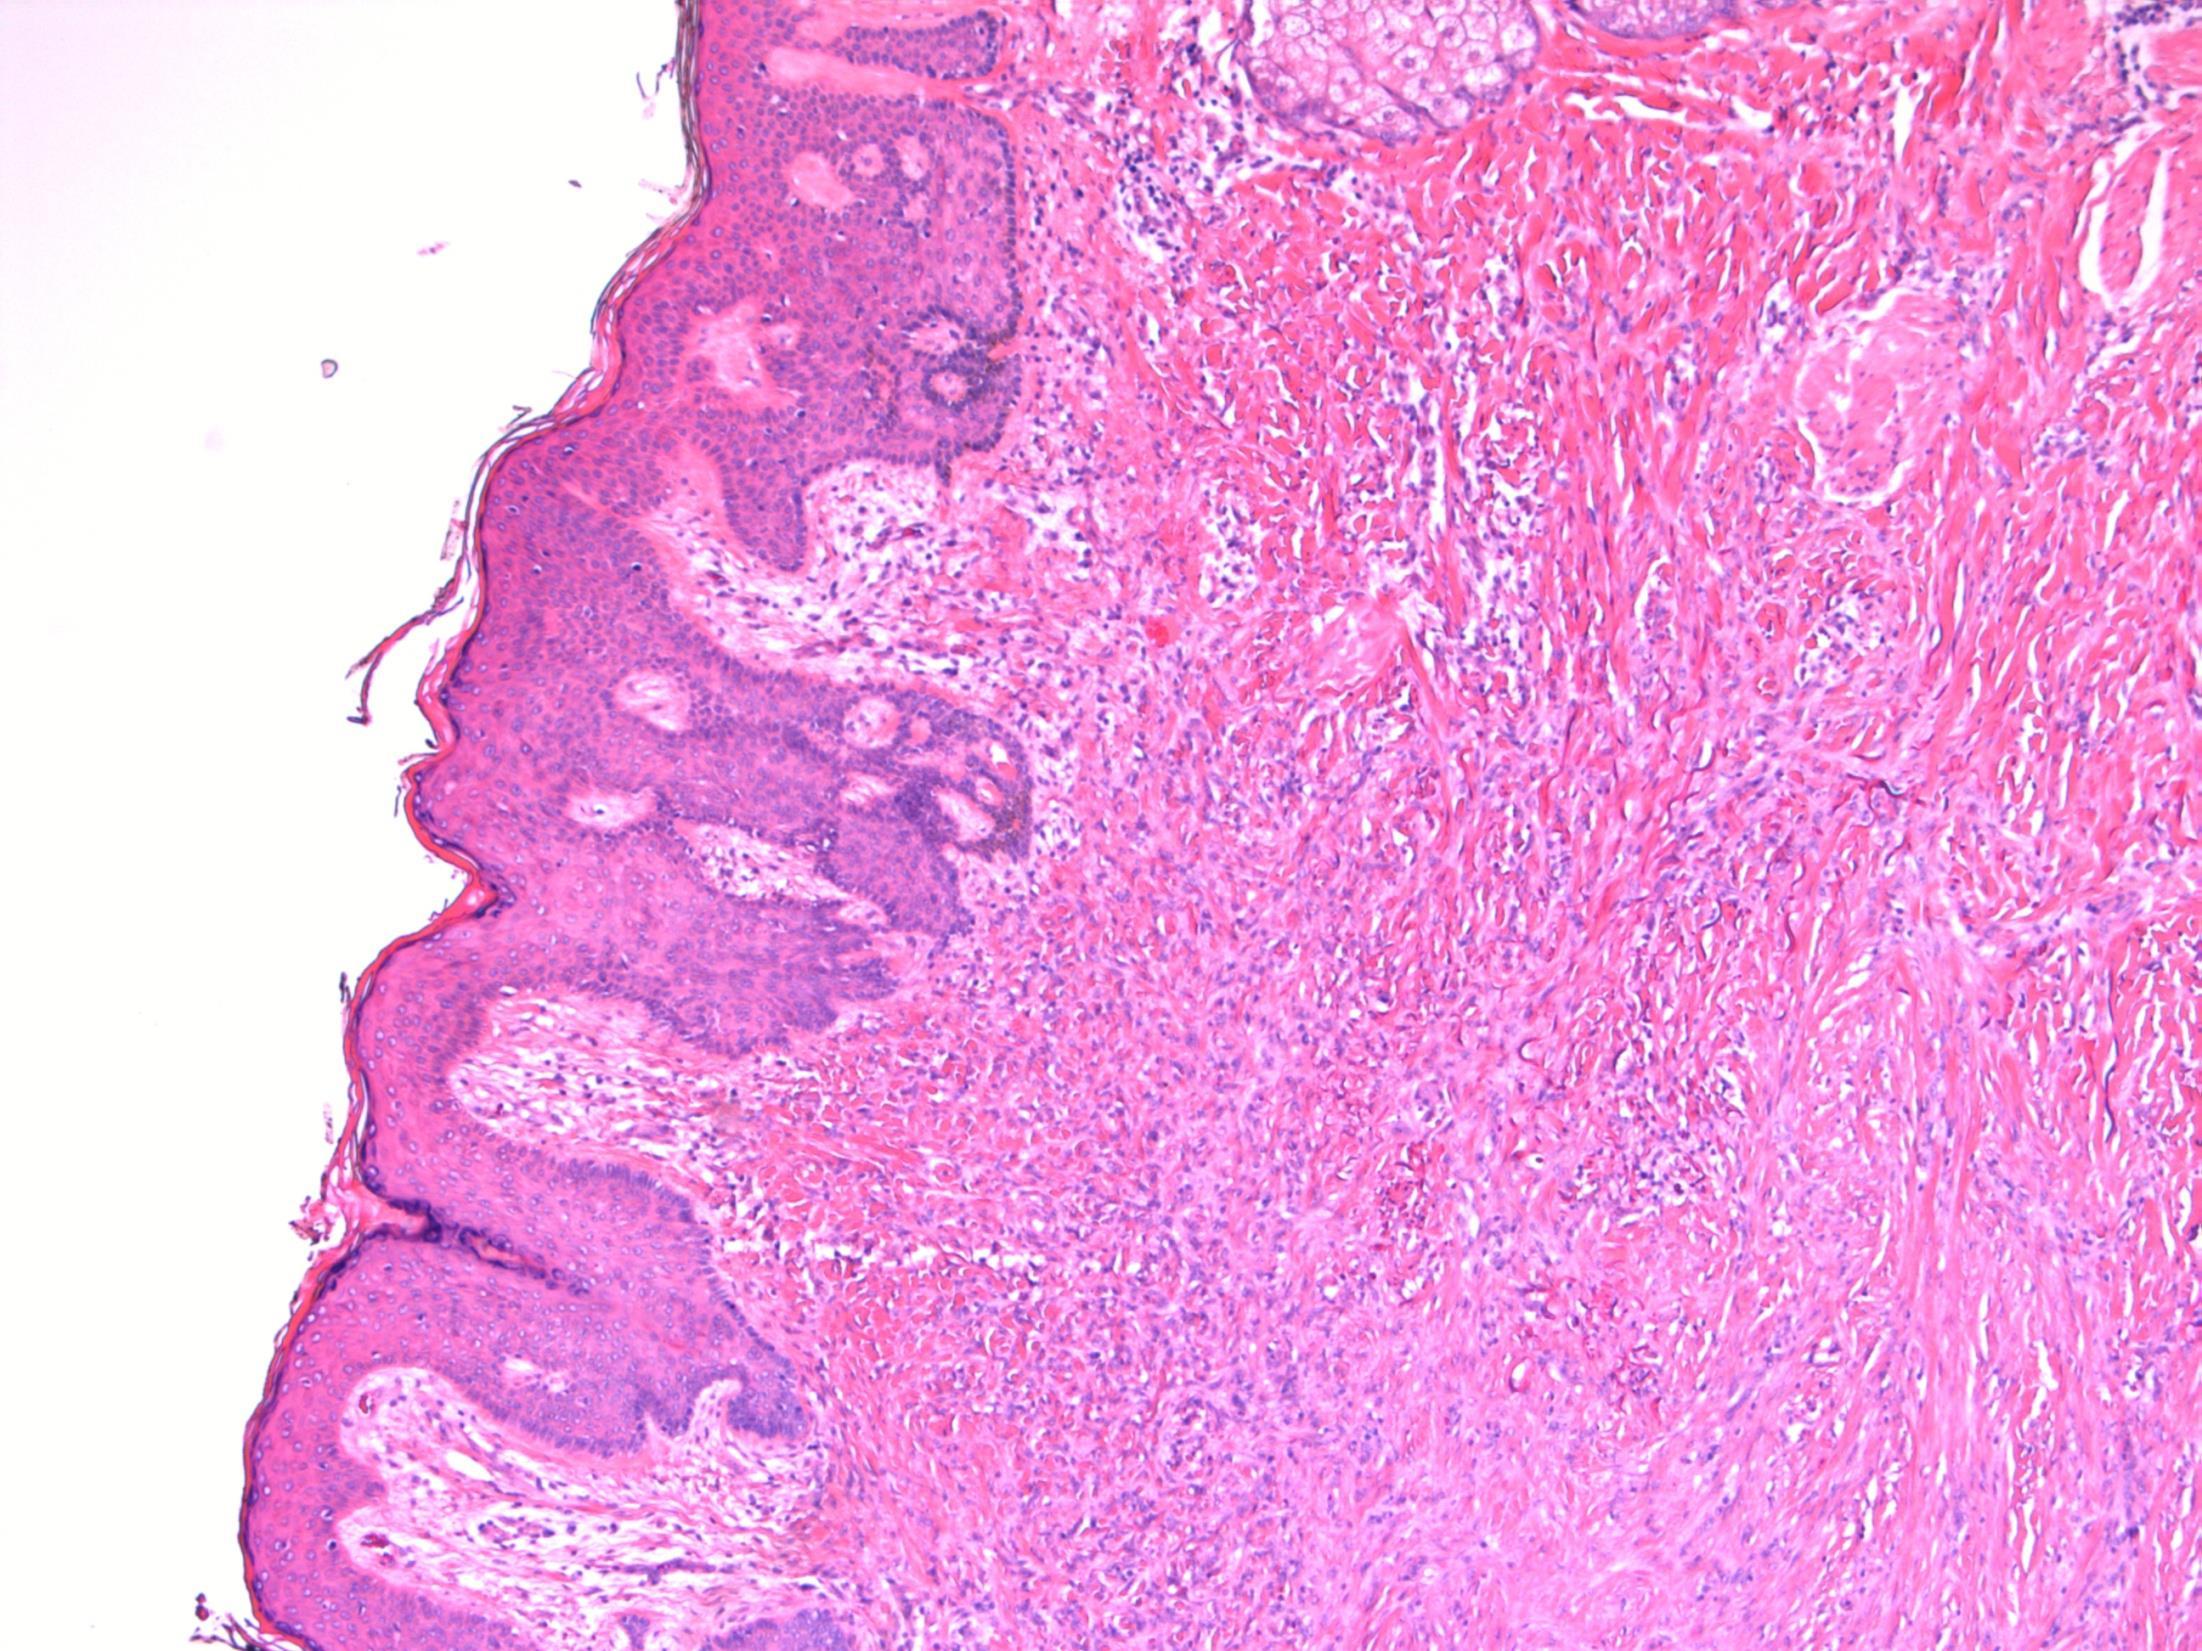

82M. Partial maxillectomy for a 3cm keratotic growth. Two previous biopsies were nonconclusive.

Case 19 •

• Maxilla – Verrucous carcinoma

Case 19

Verrucous carcinoma

Description: Abrupt transition between tumour and epithelium. Plump papillary invaginations of thickened and infolding epithelium, hyperkeratosis. Lack of cytological atypia, suprabasal mitoses. Retraction of normal epithelium at margin. Diagnosis: Verrucous carcinoma Differential Diagnosis:

Conventional SCC – cellular atypia • Squamous papilloma – more exophtyic & branching, less keratin • Reactive inflammatory epithelial hyperplasia – most difficult but rete pegs more slender and anastomosing; no mitoses; macro correlation Plan: Correlate with previous biopsies ( often quite bland so can be inconlusive) Examine further blocks for worse areas and measure margins. Comments: In head and neck – oral cavity and larynx Often large, locally aggressive, pushing margin Better prognosis than SCC

3.5 Clinical features 3.0 Potential differential diagnosis with justification (correlate history too) 2.5 Description with diagnosis 2.0 Differential diagnosis with mention of verrucous carcinoma 1.5 Uncertain, but some mention of ‘atypia’ 1.0 Benign diagnosis Case 19